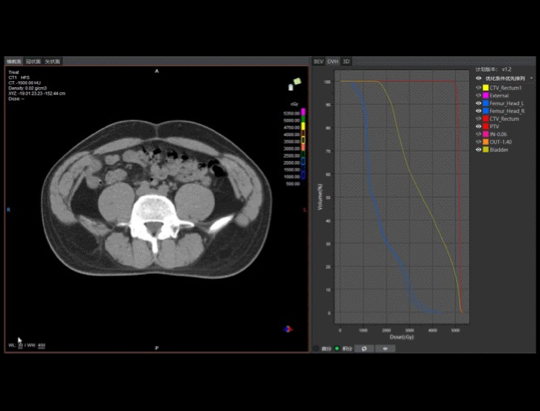

At 9:00 a.m. on March 2, 2021, the first clinical test of this idea was held: for the first time, physicians, physicists and technicians gathered in the control room to perform the first radiotherapy treatment for a rectal cancer patient using All-In-One one-stop radiotherapy technology.CT simulation positioning, intelligent outline and review modification, automatic planning, automatic reset, plan evaluation and review, CT image guidance, treatment and EPID real-time dose monitoring quality control were performed sequentially, and the whole process was completed in 23 minutes in one go, overturning the traditional first radiotherapy process that could only be completed in at least several days. This is a new tumor treatment model created by artificial intelligence technology, which has opened the era of intelligent tumor treatment 2.0.

"This is an encouraging start, and our next step will be to explore the limits of the technology and continue to optimize it with a goal of 15 minutes for the first full radiotherapy process, while expanding the application for more diseases." Director Zhang Zhen  said, "The value of this technology is not only to shorten the time in the physical sense, it can truly make patients get a more relaxed radiotherapy experience and make them feel more cared for and respected through the close cooperation of doctors, physicists and technicians."